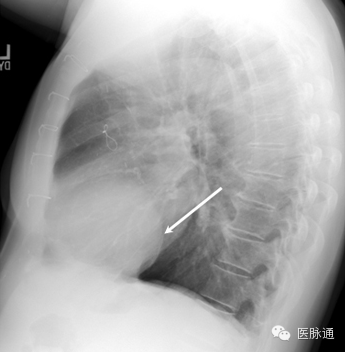

肺不张指因肺泡塌陷导致的部分肺或全肺容积减少。肺不张的原因包括肺泡内气体被吸收后造成的阻塞性肺不张,以及由于压迫、表面活性物质缺乏、肺实质形成瘢痕或胸膜脏层和壁层不再接触造成的非阻塞性肺不张。根据受累部位和程度不同,胸片表现存在很大差异。肺叶塌陷可以表现为叶间裂移位,塌陷肺叶部位致密影,以及纵隔向同侧移位,肋间隙变宽,膈肌升高和胸腔容积减少。心脏附近肺叶不张可以使得胸片上心脏边界不清。图15所示右中叶不张,并右心缘闭塞。

图15